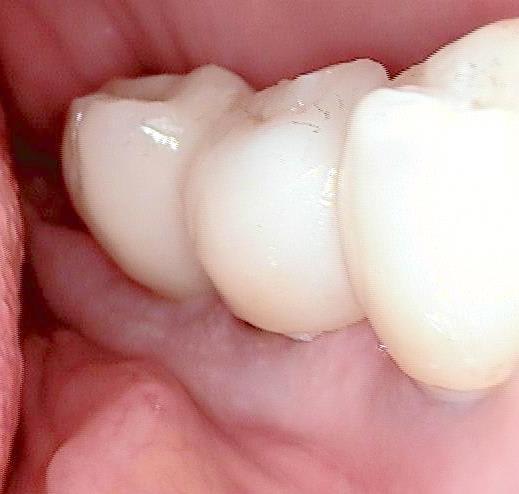

Voilà une patiente que je revois à deux ans apres la pose d'un monobloc Classic line 3,5/12mm et prep cap zircone 12 degres 2/2 en 24.

La dent 25 était une couronne massive (dent à tenon type richmond) que j'ai taillé en inlay core.

Pour répondre à Céramik, oui la zircone se taille en bouche ( fraise Komet spécifique recommandées verte et blanche..mais tout diamant fait l'affaire). A la pose des céramo metalliques on observe la prep cap zircone au niveau du joint de

la couronne.

Radios 1,2,3 photo 1= jour de la pose de l'implant.

radio 4 photo 2 et 3= 8 semaines post pose de l'implant, ceramiques scéllées.

Radio 6, photo 4 et 5 controle à 24 mois.

Deux ans plus tard, la gencive a recouvert la zircone et on observe à la radio un gain osseux au niveau des micros spires.